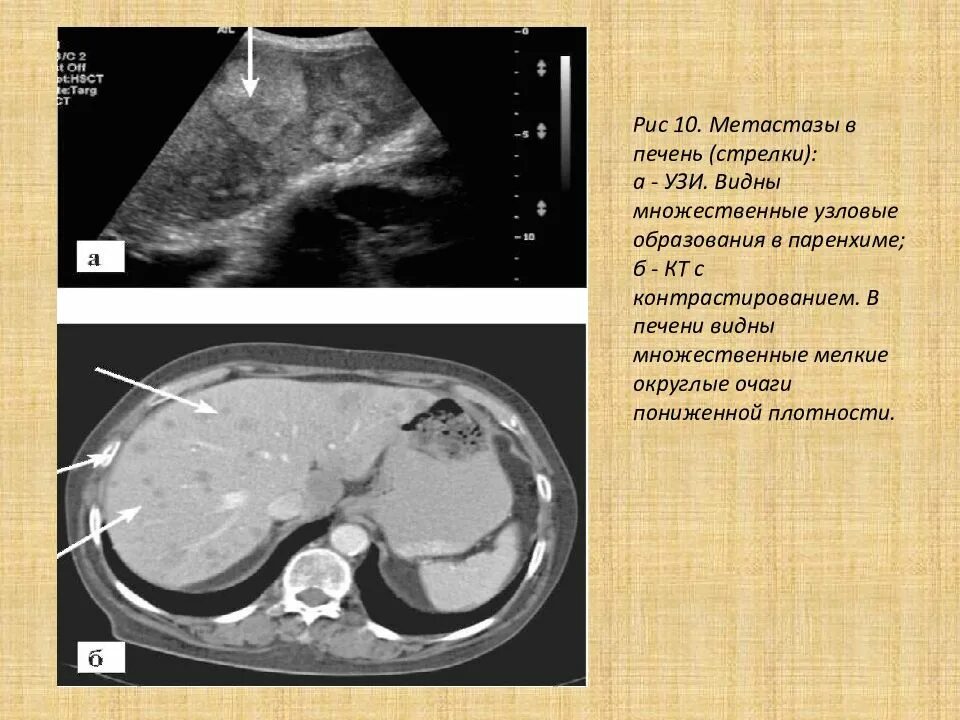

Метастазы печени какие